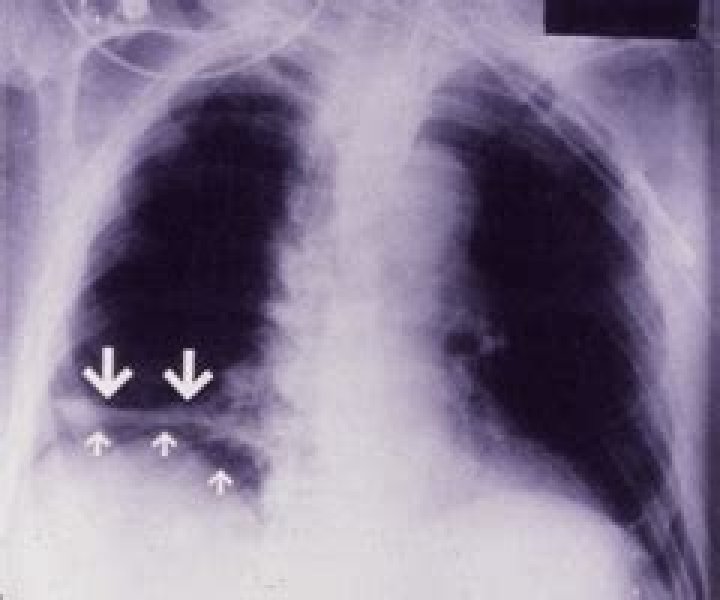

Also called discoid or subsegmental atelectasis, this type is seen most commonly on chest radiographs. Platelike atelectasis probably occurs because of obstruction of a small bronchus and is observed in states of hypoventilation, pulmonary embolism, or lower respiratory tract infection.